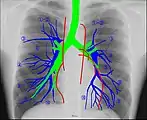

Human chest radiographic anatomy.

Human chest radiographic anatomy.

Radioanatomy (x-ray anatomy) is anatomy discipline which involves the study of anatomy through the use of radiographic films.[1] The x-ray film represents two-dimensional image of a three-dimensional object due to the summary projection of different anatomical structures onto a planar surface.

It requires certain skills for the correct interpretation of such images. Radiological anatomy is a necessary component of training for radiologists as well as medical students.